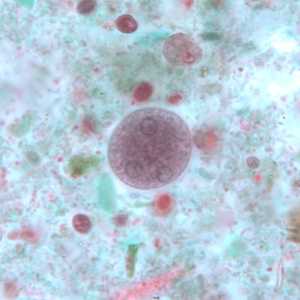

E. coli cysts stained with trichrome.

Figure A: Immature cyst of E. coli, stained with trichrome. Notice the presence of only two nuclei, and a large glycogen vacuole.

Figure B: Mature cyst of E. coli, stained with trichrome. Five nuclei are visible in this focal plane.

Figure C: Mature cyst of E. coli, stained with trichrome. In this specimen, at least five nuclei are visible in the shown focal plane.

Figure D: Mature cyst of E. coli, stained with trichrome. In this specimen, at least five nuclei are visible in the shown focal plane.

Figure E: Mature cyst of E. coli, stained with trichrome. This figure and Figure F represent the same cyst shown in two different focal planes. Eight nuclei can be seen between the two focal planes. Also, above the cyst in this figure, a trophozoite of Endolimax nana can be seen.

Figure F: Mature cyst of E. coli, stained with trichrome. This figure and Figure E represent the same cyst shown in two different focal planes. Eight nuclei can be seen between the two focal planes.